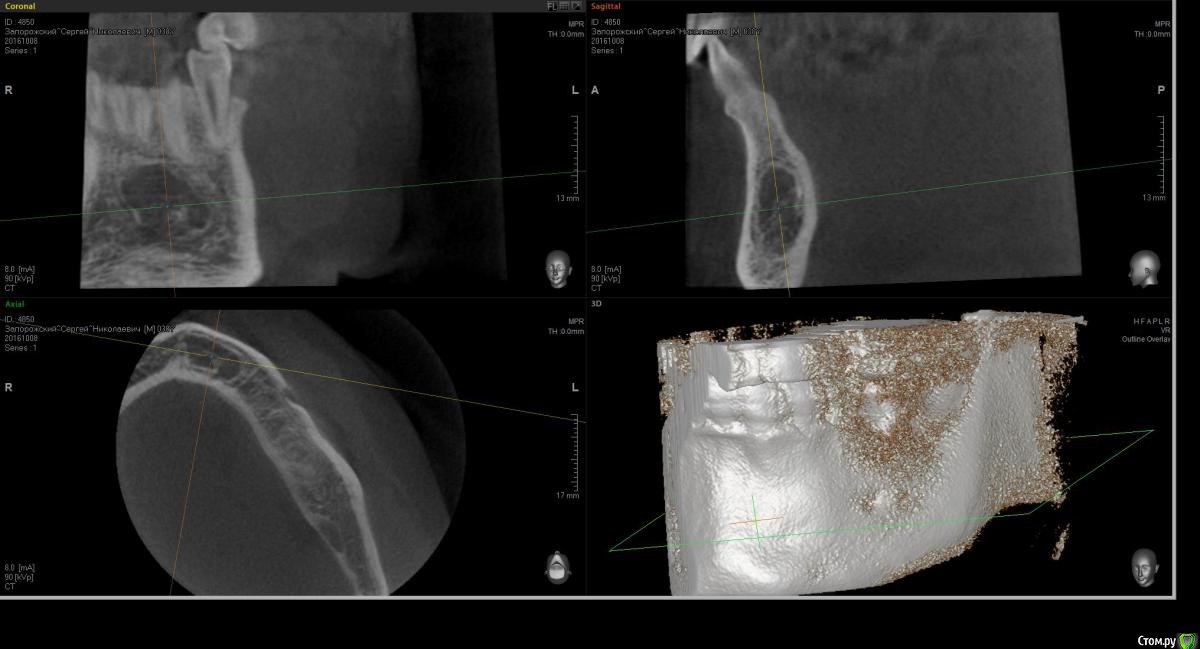

Kostoprav Опубликовано 11 октября, 2016 Поделиться Опубликовано 11 октября, 2016 жалоб никаких нет, травмы в прошлом отрицает, зубы интактные, живие.кто что думает уважаемые коллеги? Ссылка на комментарий

Maxfac Опубликовано 11 октября, 2016 Поделиться Опубликовано 11 октября, 2016 Мысли о трепано-биопсии. 2 Ссылка на комментарий

Nazim_NV86 Опубликовано 11 октября, 2016 Поделиться Опубликовано 11 октября, 2016 Мысли о трепано-биопсии. Скорее всего нарвётесь на пустоту и биоптатом будет воздух. Вопрос к костоправу: больше нигде на кт похожего нет? Остеопороз? Химиотерапия? Ссылка на комментарий

Maxfac Опубликовано 11 октября, 2016 Поделиться Опубликовано 11 октября, 2016 Скорее всего нарвётесь на пустоту и биоптатом будет воздух. Вопрос к костоправу: больше нигде на кт похожего нет? Остеопороз? Химиотерапия?Что также будет вполне ценной находкой для дифдиагноза. Через трепанационное окно можно взять и кусок оболочки. Мысли о направлении к онкологуНикогда не понимал поспешности при принятии такого решения. Сама дорога к онкологу для многих сродни эшафоту, а признаков зла на данной КТ нет. 2 Ссылка на комментарий

Kostoprav Опубликовано 11 октября, 2016 Автор Поделиться Опубликовано 11 октября, 2016 Скорее всего нарвётесь на пустоту и биоптатом будет воздух.Вопрос к костоправу: больше нигде на кт похожего нет? Остеопороз? Химиотерапия? на кт в\ч без особенностей , н\ч есть только этот сегмент, анамнез тоже без особенностей. Ссылка на комментарий

Доктор Добрых Дел Опубликовано 12 октября, 2016 Поделиться Опубликовано 12 октября, 2016 признаков зла на данной КТ нет. Зла может и нет, но меня здесь настораживает деформация челюсти в области данного образования, поэтому лично я бы не стал его с ходу сверлить. 1 Ссылка на комментарий

Kostoprav Опубликовано 12 октября, 2016 Автор Поделиться Опубликовано 12 октября, 2016 деформации нет, есть незначительное чувство дискомфорта при надавливании на эту область Ссылка на комментарий

ПалСаныч Опубликовано 21 октября, 2016 Поделиться Опубликовано 21 октября, 2016 Если бы ко мне попал такой пациент, я бы под местной анестезией пародонтальным разрезом отслоил бы лоскут, пропилил бы окошко и постарался б удалит не прорвав облочку ( ну чисто для красоты процесса)). Заполнил бы отцентрифугированной соплей, закрыл мембраной и зашил. Удаленный материал на гист.исследование. Принятие решение о дальнейшей тактике после получения результата. 1 Ссылка на комментарий